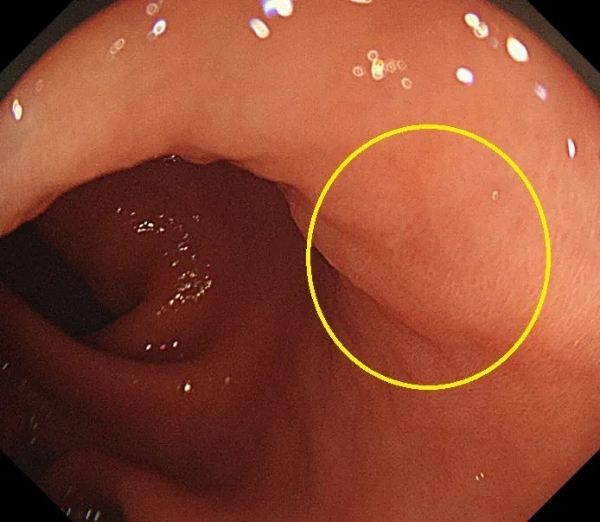

普通胃镜,主要用于发现肉眼下容易辨别的病变,却不容易发现很多隐藏在萎缩性胃炎背景下的微小早期癌变。

(病变位于黄圈中央位置,普通胃镜很难发现)